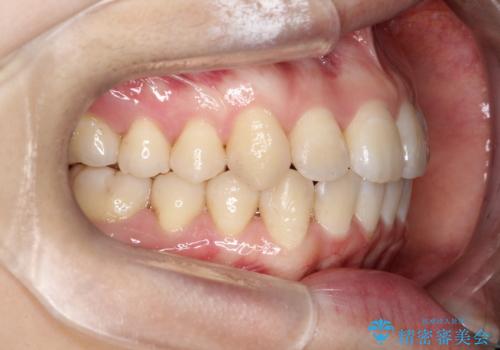

【インビザライン】前歯の凸凹をなおしたい

- 前歯の凸凹をなおしたいことを主訴にインビザラインにて矯正治療を行いました。

患者様にしっかりとインビザラインを使用して頂けたことで綺麗な仕上がりとなりました。